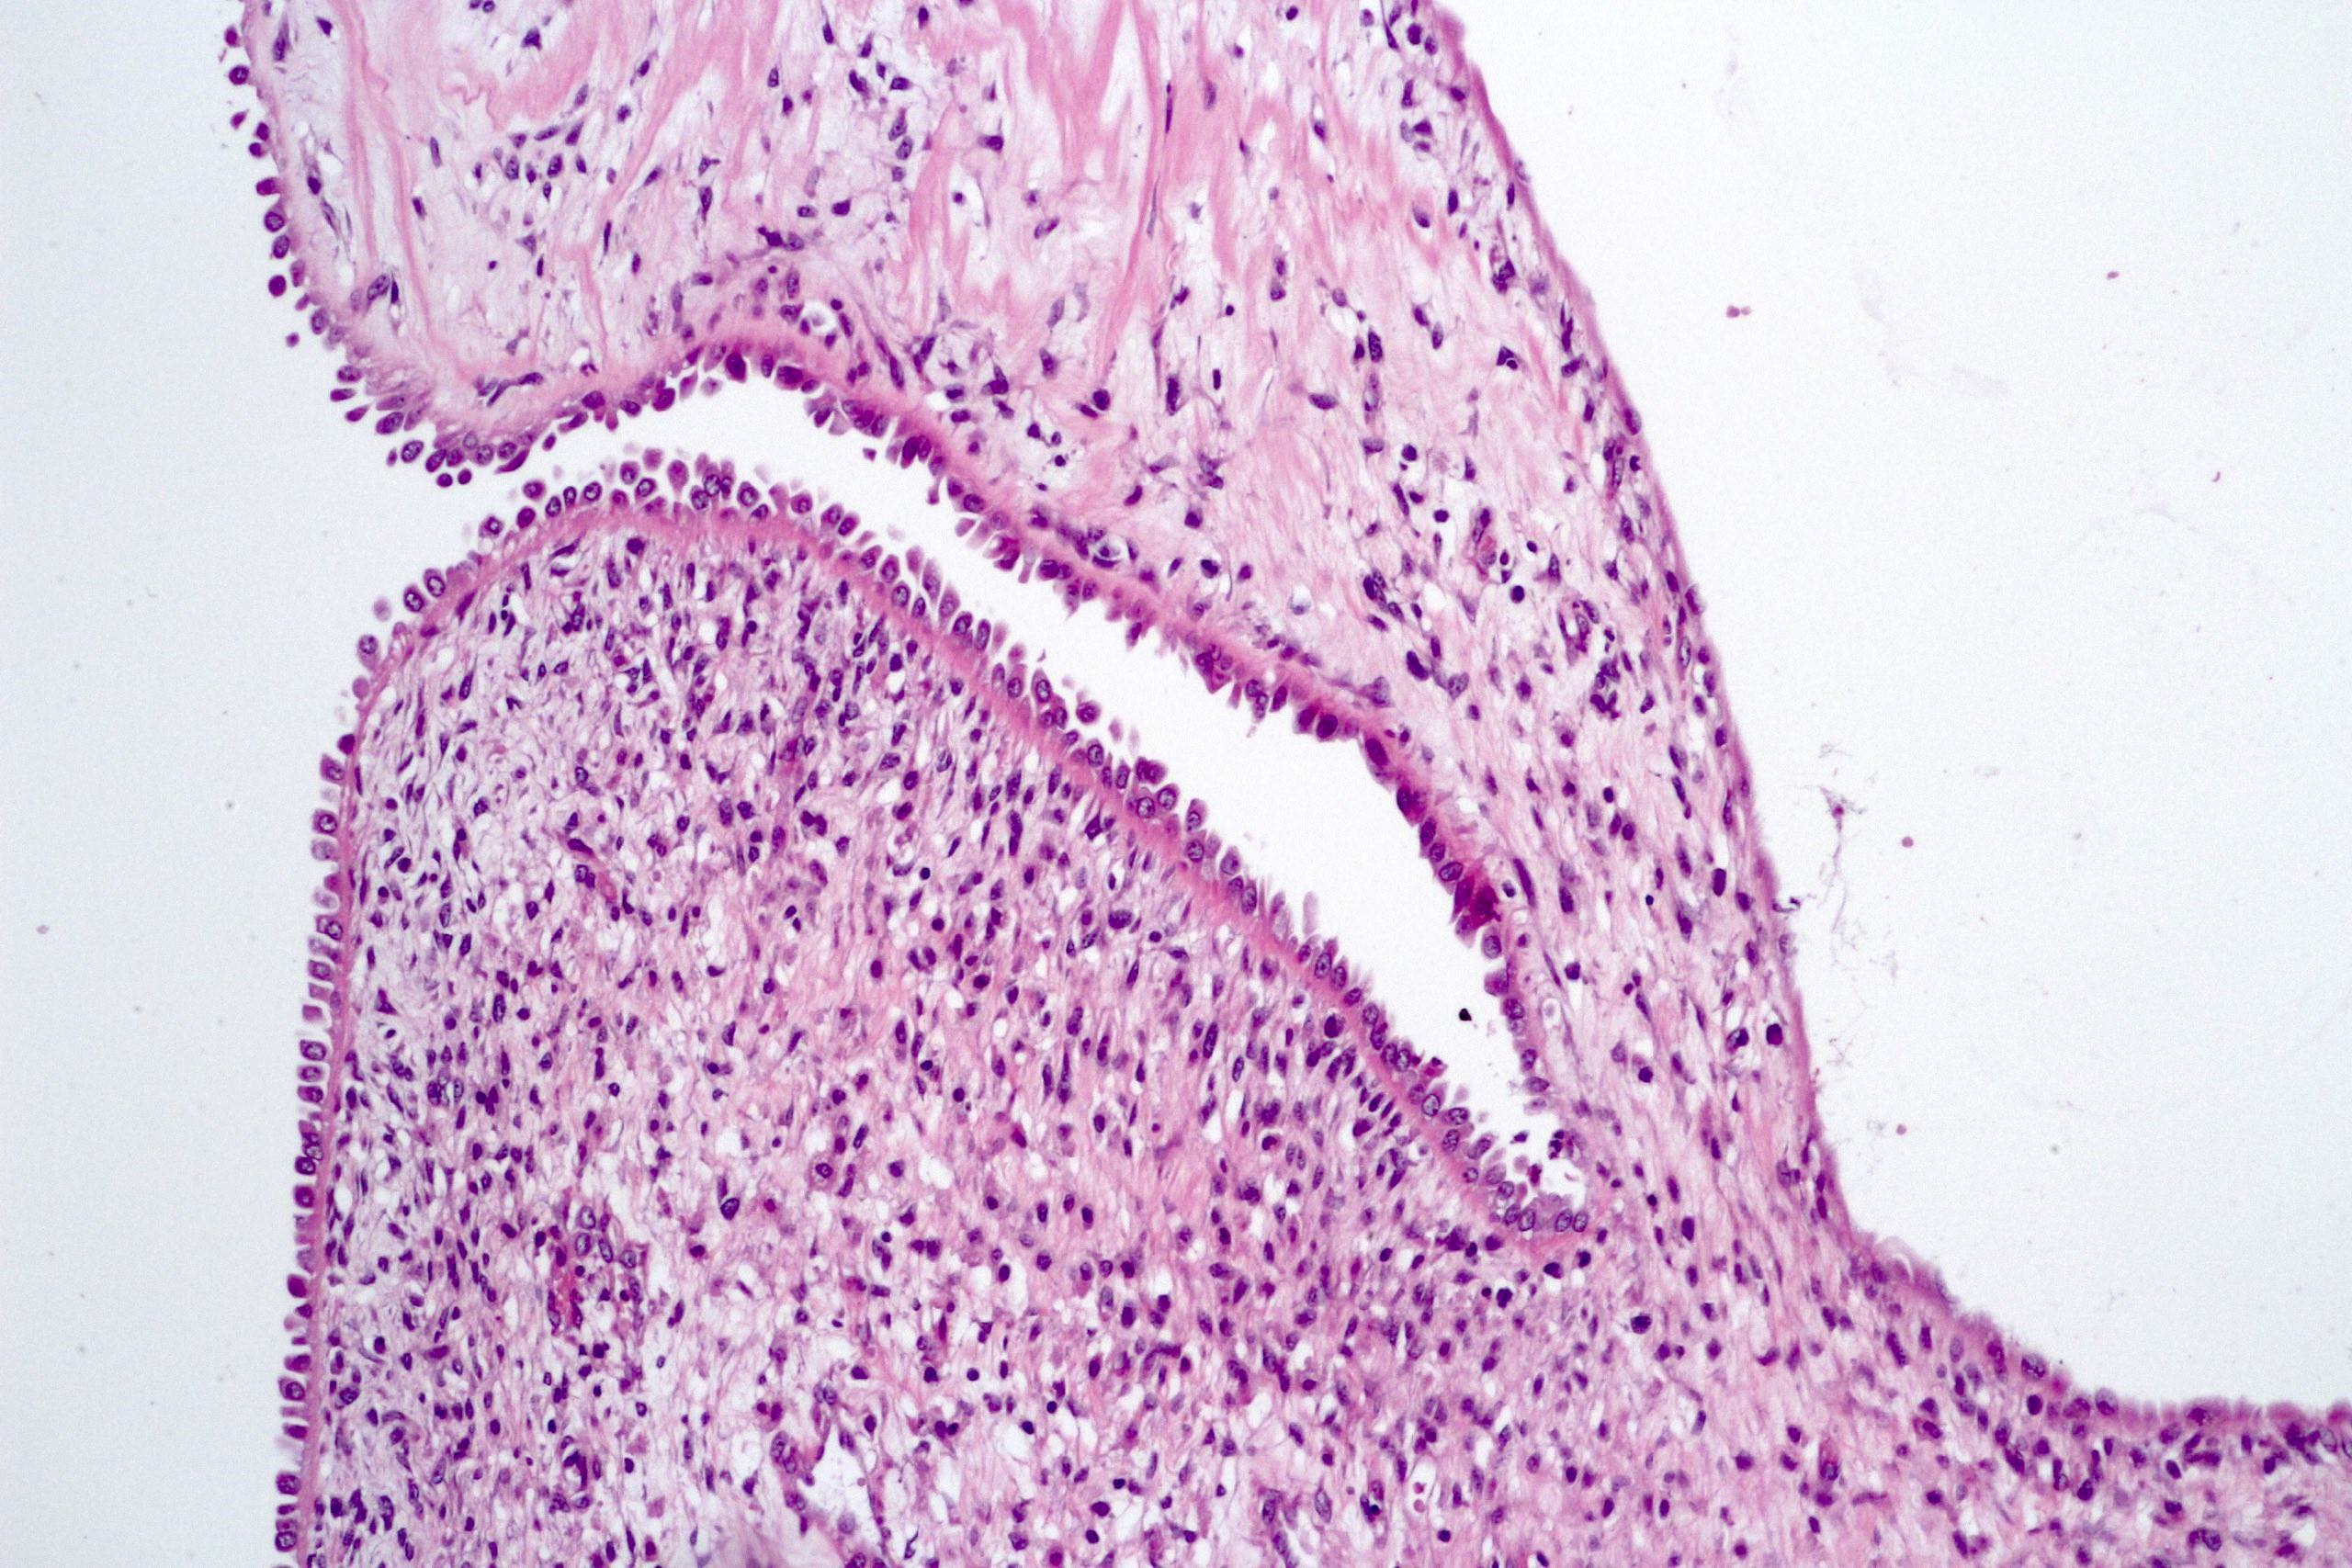

Microscopic (histologic) description

- Cysts lined with flat / cuboidal / hobnail cells (or are denuded)

- Epithelial elements consist mainly of mature and immature / abortive tubules and small papillae resembling immature glomeruli

- Key histological findings of the variably cellular septa include

- Nephroblastomatous epithelial elements

- Islands of undifferentiated blastema and differentiated mesenchymal elements (skeletal muscle and less often cartilage and fat) (J Urol 2010;183:1585)

- Focally, the septal elements may protrude into the cystic spaces in microscopic papillary folds

Microscopic (histologic) images

Contributed by Americo Brilhante, M.D. and Daniel Athanazio, M.D., Ph.D.